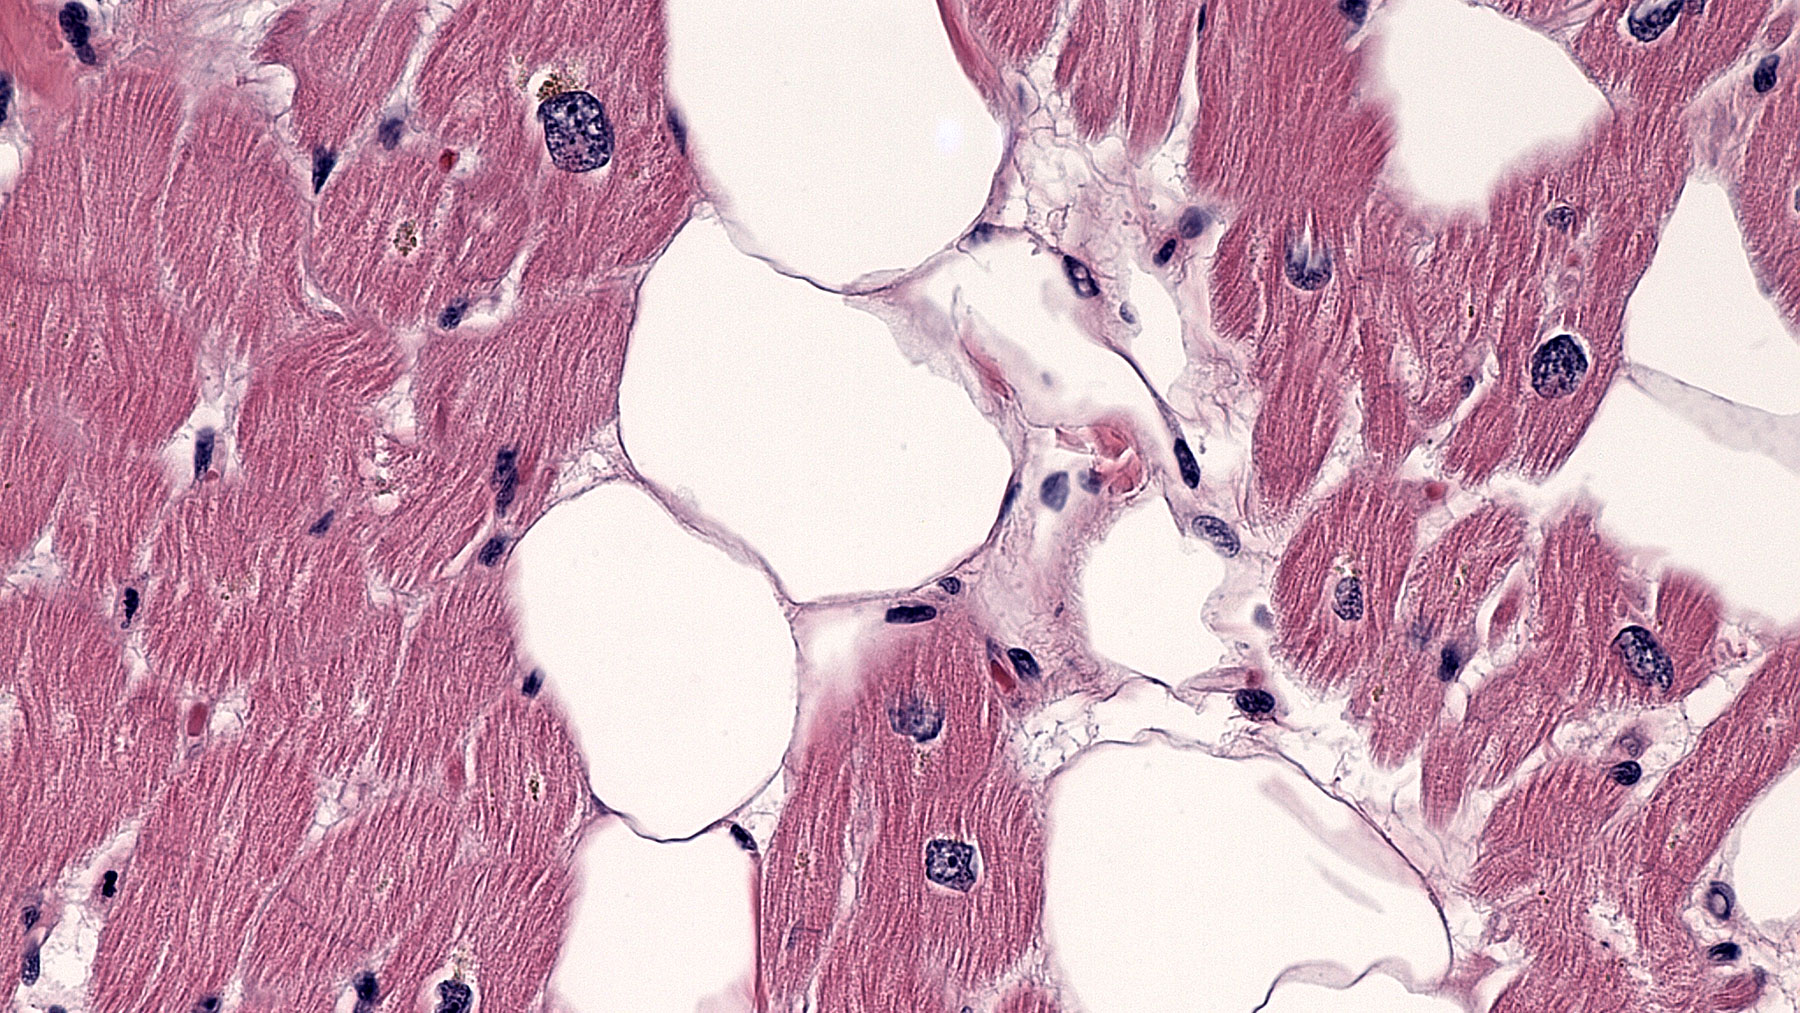

Figure F. H&E x40

Histology: H&E staining (Figures C-F) from the explanted heart shows patchy replacement of the myocardium by adipose tissue.